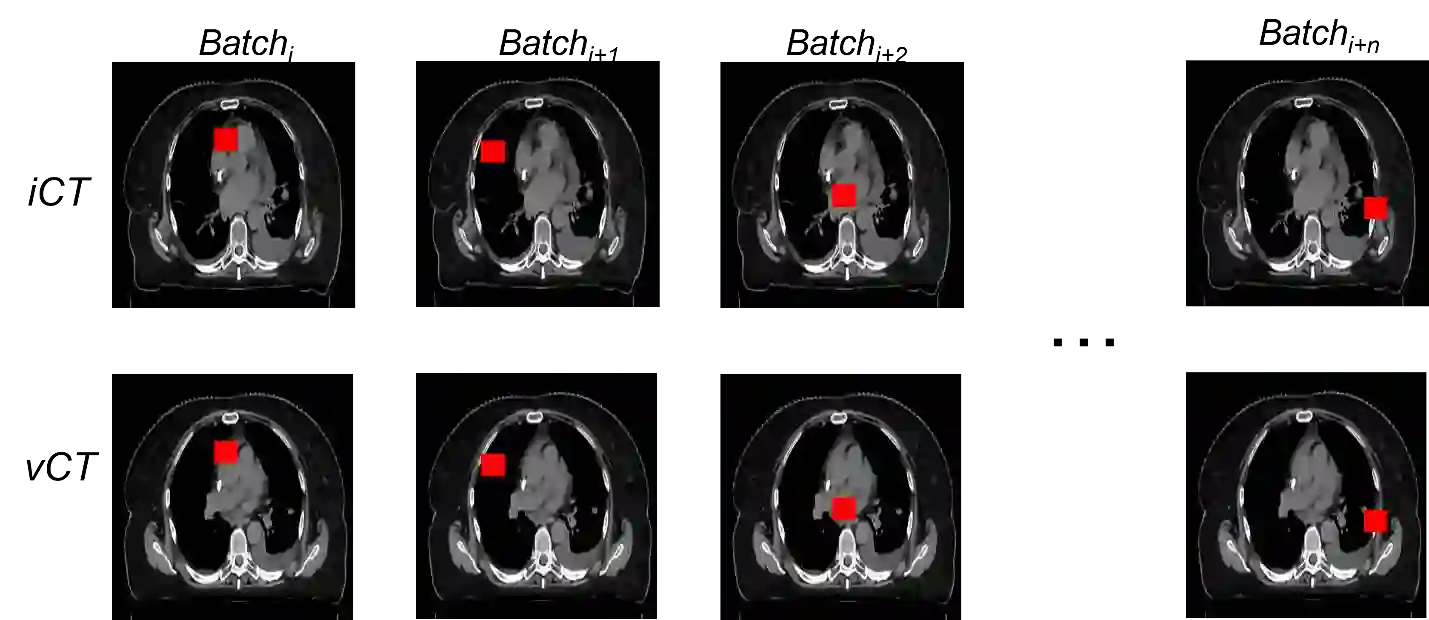

Purpose: In some proton therapy facilities, patient alignment relies on two 2D orthogonal kV images, taken at fixed, oblique angles, as no 3D on-the-bed imaging is available. The visibility of the tumor in kV images is limited since the patient's 3D anatomy is projected onto a 2D plane, especially when the tumor is behind high-density structures such as bones. This can lead to large patient setup errors. A solution is to reconstruct the 3D CT image from the kV images obtained at the treatment isocenter in the treatment position. Methods: An asymmetric autoencoder-like network built with vision-transformer blocks was developed. The data was collected from 1 head and neck patient: 2 orthogonal kV images (1024x1024 voxels), 1 3D CT with padding (512x512x512) acquired from the in-room CT-on-rails before kVs were taken and 2 digitally-reconstructed-radiograph (DRR) images (512x512) based on the CT. We resampled kV images every 8 voxels and DRR and CT every 4 voxels, thus formed a dataset consisting of 262,144 samples, in which the images have a dimension of 128 for each direction. In training, both kV and DRR images were utilized, and the encoder was encouraged to learn the jointed feature map from both kV and DRR images. In testing, only independent kV images were used. The full-size synthetic CT (sCT) was achieved by concatenating the sCTs generated by the model according to their spatial information. The image quality of the synthetic CT (sCT) was evaluated using mean absolute error (MAE) and per-voxel-absolute-CT-number-difference volume histogram (CDVH). Results: The model achieved a speed of 2.1s and a MAE of <40HU. The CDVH showed that <5% of the voxels had a per-voxel-absolute-CT-number-difference larger than 185 HU. Conclusion: A patient-specific vision-transformer-based network was developed and shown to be accurate and efficient to reconstruct 3D CT images from kV images.